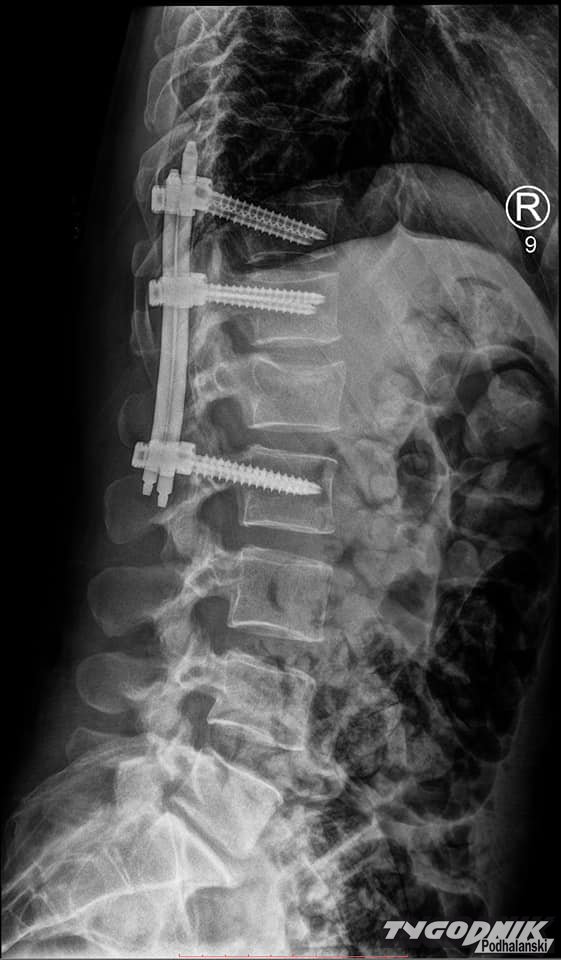

W bezpośredniej konsekwencji zderzenia i pociągnięcia w dół złamałam kręgosłup (niestabilne złamanie, które w każdej chwili mogło doprowadzić do paraliżu) znalazłam się na SORze, a następnie na oddziale ortopedycznym w szpitalu w Nowym Targu. Aktualnie jestem po trwającej cztery godziny operacji stabilizacji kręgosłupa, bogatsza o nowe doświadczenia (m. in. bóle pooperacyjne, jakich nie życzę najgorszym wrogom) i sześć tytanowych śrub stabilizujących złamany krąg L1." - opisuje kobieta na Facebooku.